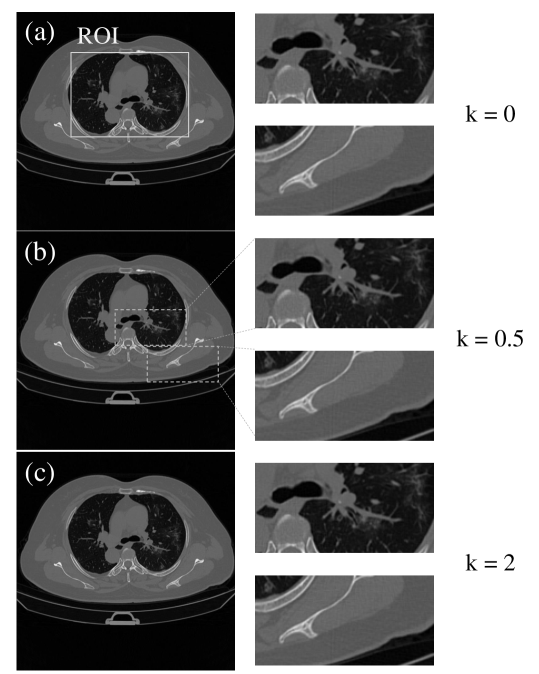

The effectiveness of the proposed weights is validated on real CT slices for a wide range of by mimicking a GEGCT scan using clinical lung CT dataset. 32 In order to get the same geometric magnification ratio in the experiments, is fixed at mm and is fixed at mm while varies. Taking polynomial weights as examples in Fig. 8, there is no obvious difference among = 0, 0.5 and 2. The zoomed-in images in Fig. 8 show the same level of crisp detail of texture. As listed in Table 3, in the selected ROI, the HU accuracy of the reconstruction by using the proposed polynomial weights is consistent with that of the standard equiangular fan-beam CT.

| k | 0* | 0.5 | 1 | 1.5 | 2 |

| PSNR(dB) | 37.59 | 37.60 | 37.59 | 37.59 | 37.59 |

| SSIM | 0.979 | 0.979 | 0.979 | 0.979 | 0.979 |

-

*

The traditional equiangular fan-beam CT